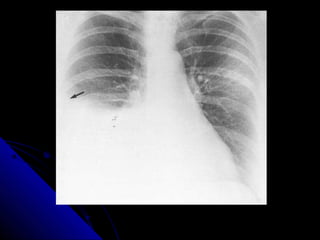

PPuullmmoonnaarryy eemmbboolliissmm

CChheecckk tthhee tteecchhnniiccaall qquuaalliittyy..

SSeeggmmeennttaall bbllaacckknneessss..

RRaarreellyy wwhhoollee lluunngg bbllaacckknneessss…………..ssttoopp

llooookkiinngg ssttaarrtt ttrreeaattmmeenntt..

IInnccrreeaasseedd ssiizzee ooff tthhee ppuullmmoonnaarryy aarrtteerryy aanndd

rriigghhtt hheeaarrtt..

PPuullmmoonnaarryy eemmbboolliissmm CChheecckktthhee tteecchhnniiccaall qquuaalliittyy.. SSeeggmmeennttaall bbllaacckknneessss.. RRaarreellyy wwhhoollee lluunngg bbllaacckknneessss…………..ssttoopp llooookkiinngg ssttaarrtt ttrreeaattmmeenntt.. IInnccrreeaasseedd ssiizzee ooff tthhee ppuullmmoonnaarryy aarrtteerryy aanndd rriigghhtt hheeaarrtt.. 51